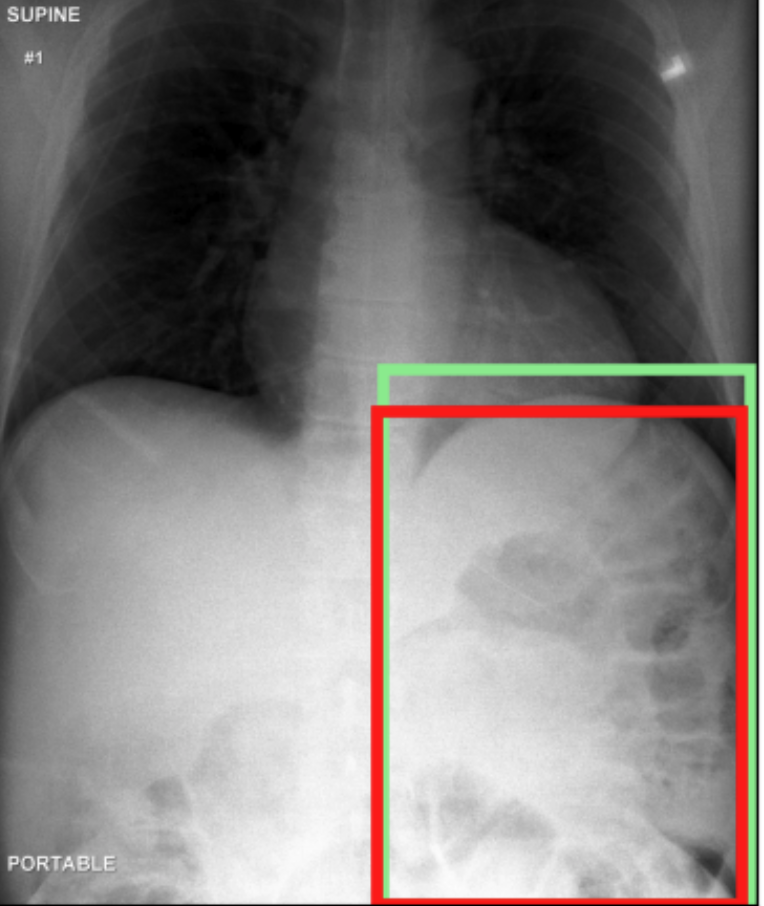

4.3.3 Visual grounding

In this section, we evaluate RadVLM’s visual grounding capabilities, which could help clinicians localize specific regions or pathologies on a CXR. This is particularly useful once a pathology has already been identified – either by a radiologist’s input or through our previously described AI tasks – since it allows one to pinpoint exactly where the abnormality appears on the image.

We report performance metrics for the three main grounding tasks RadVLM was trained on: anatomical grounding using the Chest Imagenome test set, abnormality grounding using the VinDr-CXR test set, and phrase grounding using the MS-CXR test set (Table 1). For each task, we use mean Average Precision (mAP) as our primary evaluation metric.

Our results show that RadVLM performs well at localizing anatomical regions (e.g., “right lung”, “aortic arch”, illustrated in Figure 5a), achieving a mAP of 85.8 %, by far surpassing the other CXR grounding models (Table 4). This advantage is partly explained by including the Chest Imagenome dataset (and thus the anatomical grounding task) in the training set, which CheXagent and MAIRA-2 did not leverage. However, it remains a key feature for any grounding model to possess a fine-grained understanding of CXR anatomy.

For the abnormality grounding task, RadVLM is less consistent (Figure 5b), likely due to higher sparsity of abnormality locations and labels, yet it still achieves best performance (Table 4). For the phrase grounding task, while MAIRA-2 and CheXagent demonstrate great performance, RadVLM surpasses them with a mAP of 81.8% (Table 4), presumably benefiting from the newly released PadChest-GR dataset (Castro et al.,, 2024) used for training.

Overall, these results show that our instruction tuning strategy for visual grounding (covering three essential tasks), combined to a modern VLM backbone, offers a promising avenue to help clinicians localize anatomical and pathological features during a CXR exam. Furthermore, providing fine-grained details within an LLM-generated output may also enhance the ability to answer grounded questions in a multi-turn setting, as we explore next.

a. Anatomical grounding

silhouette

junction

structures

lung

abdomen

mediastinum

arch

b. Abnormality grounding

thickening

fibrosis

enlargement

lung disease